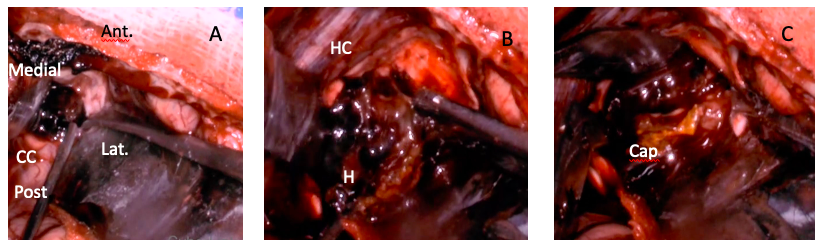

Figura 1. A: RMN secuencia T1 corte sagital donde se observó una lesión lobulada heterogénea con áreas hiperintensas comprometiendo cuerpo calloso y tercer ventrículo. B: RMN secuencia T2 corte axial donde se evidencia compromiso de ganglios de la base, cápsula interna y sistema ventricular. C: TAC encéfalo sin contraste corte axial donde se evidenció lesión de voluminoso tamaño mayoritariamente hiperdensa, con compromiso de morfología ventricular y ausencia de hemoventrículo.

(Nota de autor: No se cuenta con secuencia SWAN porque la paciente concurrió a nuestro nosocomio con una RMN realizada en resonador de bajo campo en su país de origen y sin esa secuencia realizada , no se repitieron estudios previos a la cirugía.)